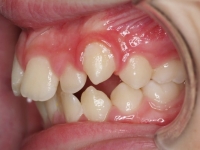

Paciente de 15 años “no le gusta su sonrisa”. La paciente presenta:

- Clase I esquelética con tendencia a Clase III

- Clase I molar

- Perfil con protusión mandibular

- Laterales enanos

- Apiñamiento

El tratamiento se hizo con brackets de autoligado y tuvo una duración de año y medio. Al finalizar, su dentista le hizo reconstrucción con carillas de los incisivos laterales 12.22.

Ahora la paciente está en contención con férulas superior e inferior más contención fija inferior.